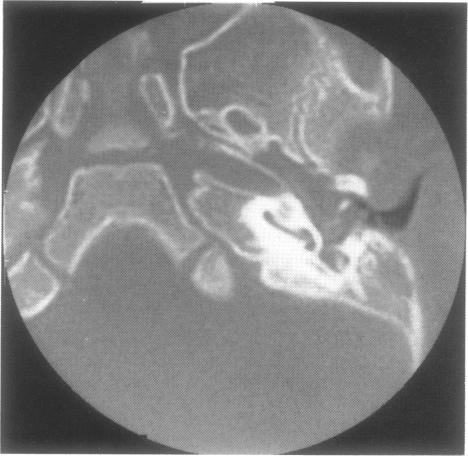

Dermoid cysts of the head and neck are rare lesions comprised of epidermal and mesodermal elements. We report a dermoid cyst presenting in the middle ear of the youngest patient reported to date. Structures of endodermal descent were also identified, but, given that the entire middle ear mucosa is of endodermal origin, specific classification as a teratoma would be imprecise. This lesion is interesting in that it did not directly involve the mastoid. Possible embryologic sites of origin are discussed.

头颈部皮样囊肿是由表皮和中胚层成分组成的罕见病变。我们报告了一例皮样囊肿,其出现在迄今报道的最年轻患者的中耳。还发现了内胚层起源的结构,但鉴于整个中耳黏膜均起源于内胚层,将其明确分类为畸胎瘤并不准确。该病变的有趣之处在于它未直接累及乳突。文中讨论了可能的胚胎起源部位。